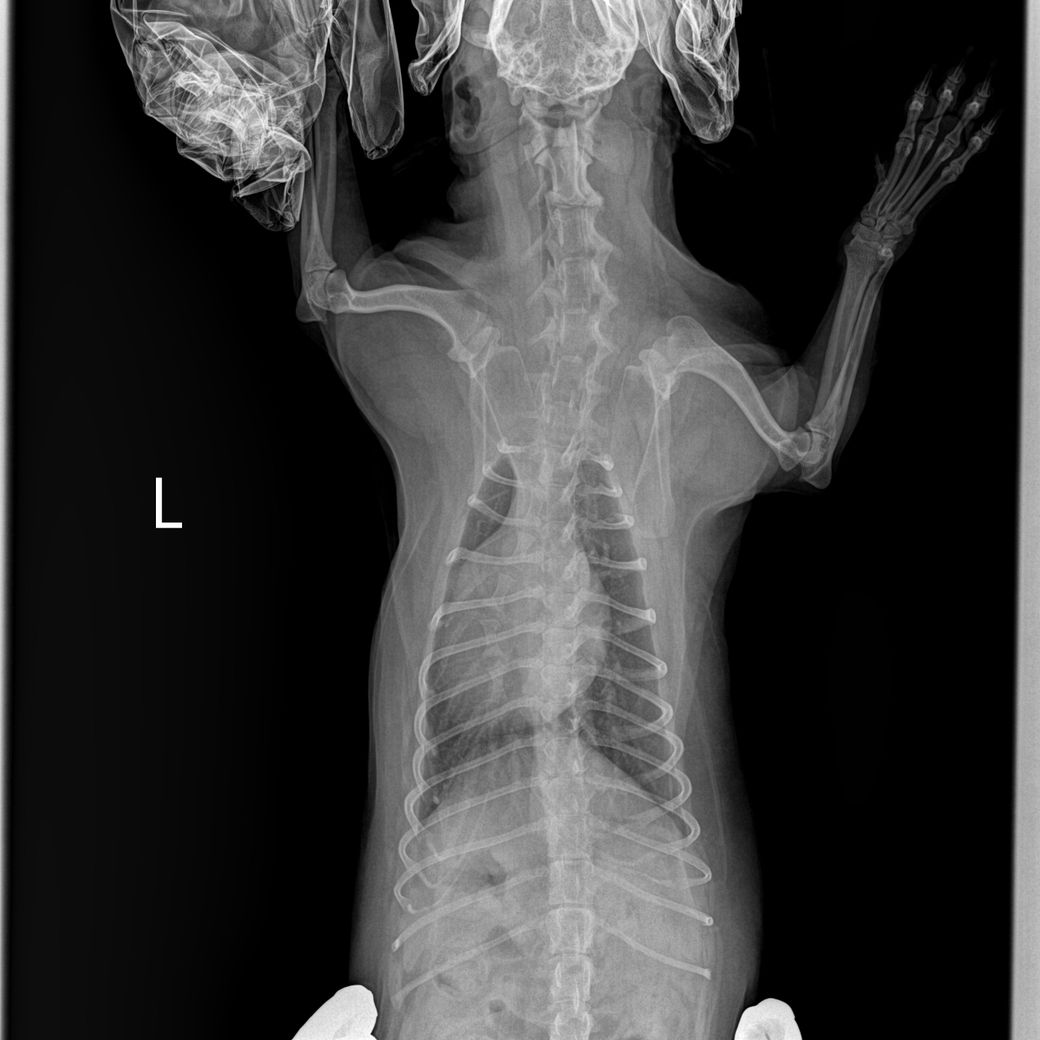

안녕하세요 강아지 건강검진을했는데 흉골이 휘었다고해서요. 첫번째사진은 1년전이고 2,3번째 사진은 이번년도 사진입니다.

혹시 이런경우 원인은 무엇인가요? 외부충격은 없었습니다..

2~3번 사진은 촬영상이 돌아가면서 흉골이 "휘어 보이는것 처럼" 보이는 것이고 실제 휜게 아닙니다. 앞에서 언급되었던 오목가슴과 같은 문제는 이 촬영상이 아닌 옆에서 촬영하는 외측상으로 판단하는것입니다.